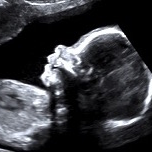

Suivi de votre grossesse avec réalisation des échographies recommandées, Prise en charge des IVG medicamenteuses (en lien avec la maternité de Beaune), infertilité, prise en charge des douleurs pelviennes (endométriose par exemple)

Diplômée en Echographie foetale et Gynécologique

Diplômée en Médecine Foetale

Agrément National pour la réalisation des échographies du Premier Trimestre de grossesse